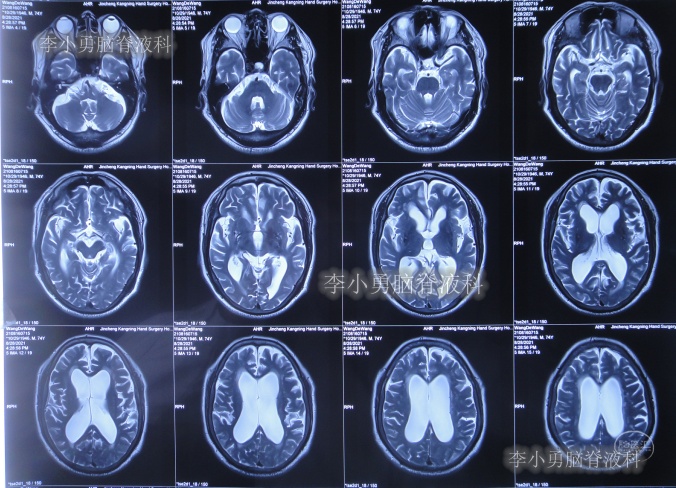

发现脑积水后8天即2020年11月6日,就诊于第2家的上海的某三甲医院,入院后再次检查(图-2)后诊断为正常压力脑积水。

图-2:2020年11月11日头部核磁